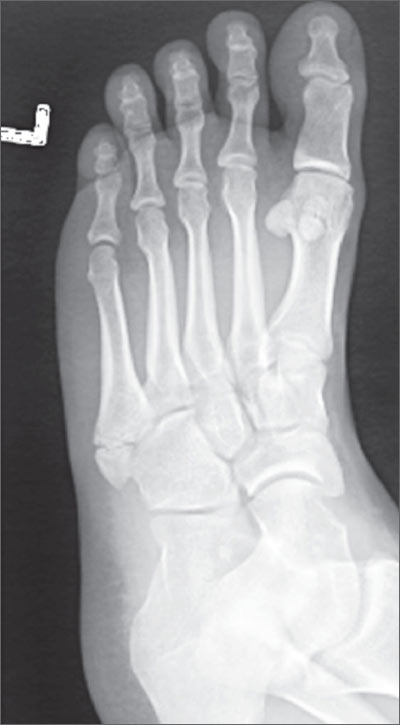

A 37-year-old man went to see his family physician (FP) after twisting his ankle the day before while playing basketball with his teenagers. The patient felt a pop and experienced immediate pain. On examination, he had tenderness over the base of his fifth metatarsal. The FP ordered an x-ray.

The x-ray revealed that the patient had a nondisplaced fracture at the base of the fifth metatarsal (also known as a dancer’s fracture). Most metatarsal fractures involve the fifth metatarsal and include avulsion fractures at the base, as seen in this patient. Fractures of the first through fourth metatarsals are less common. Diagnosis is based on the mechanism of injury/type of overuse activity and the radiographic appearance.

Treatment depends on the type of fracture. Most metatarsal fractures at the base have a good prognosis; however Jones fractures—an acute diaphyseal fracture of the fifth metatarsal—have a high rate of non-union.

In this case, the physician prescribed a walking boot with ambulation for 4 weeks. If the avulsion fracture had been displaced, however, the patient would have been referred to an orthopedist.